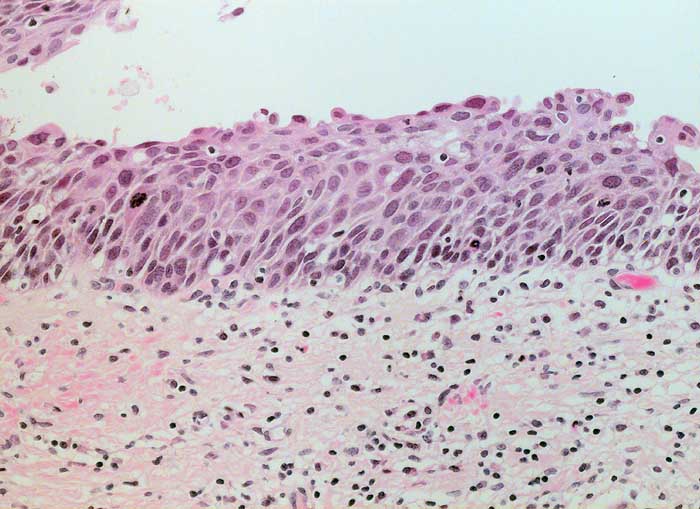

schwere Dysplasie CIN III

Portio

Portiokonisat: Auf der gesamten Epithelbreite atypisches Epithel ohne Ausreifung.